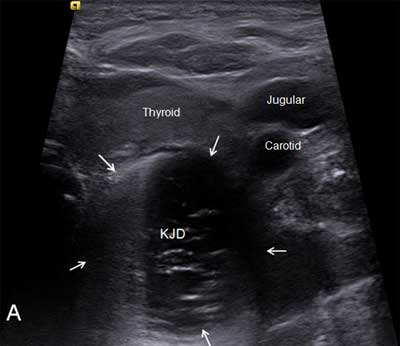

Figure A

Ultrasonographic axial section showing KJD behind the thyroid left lobe.